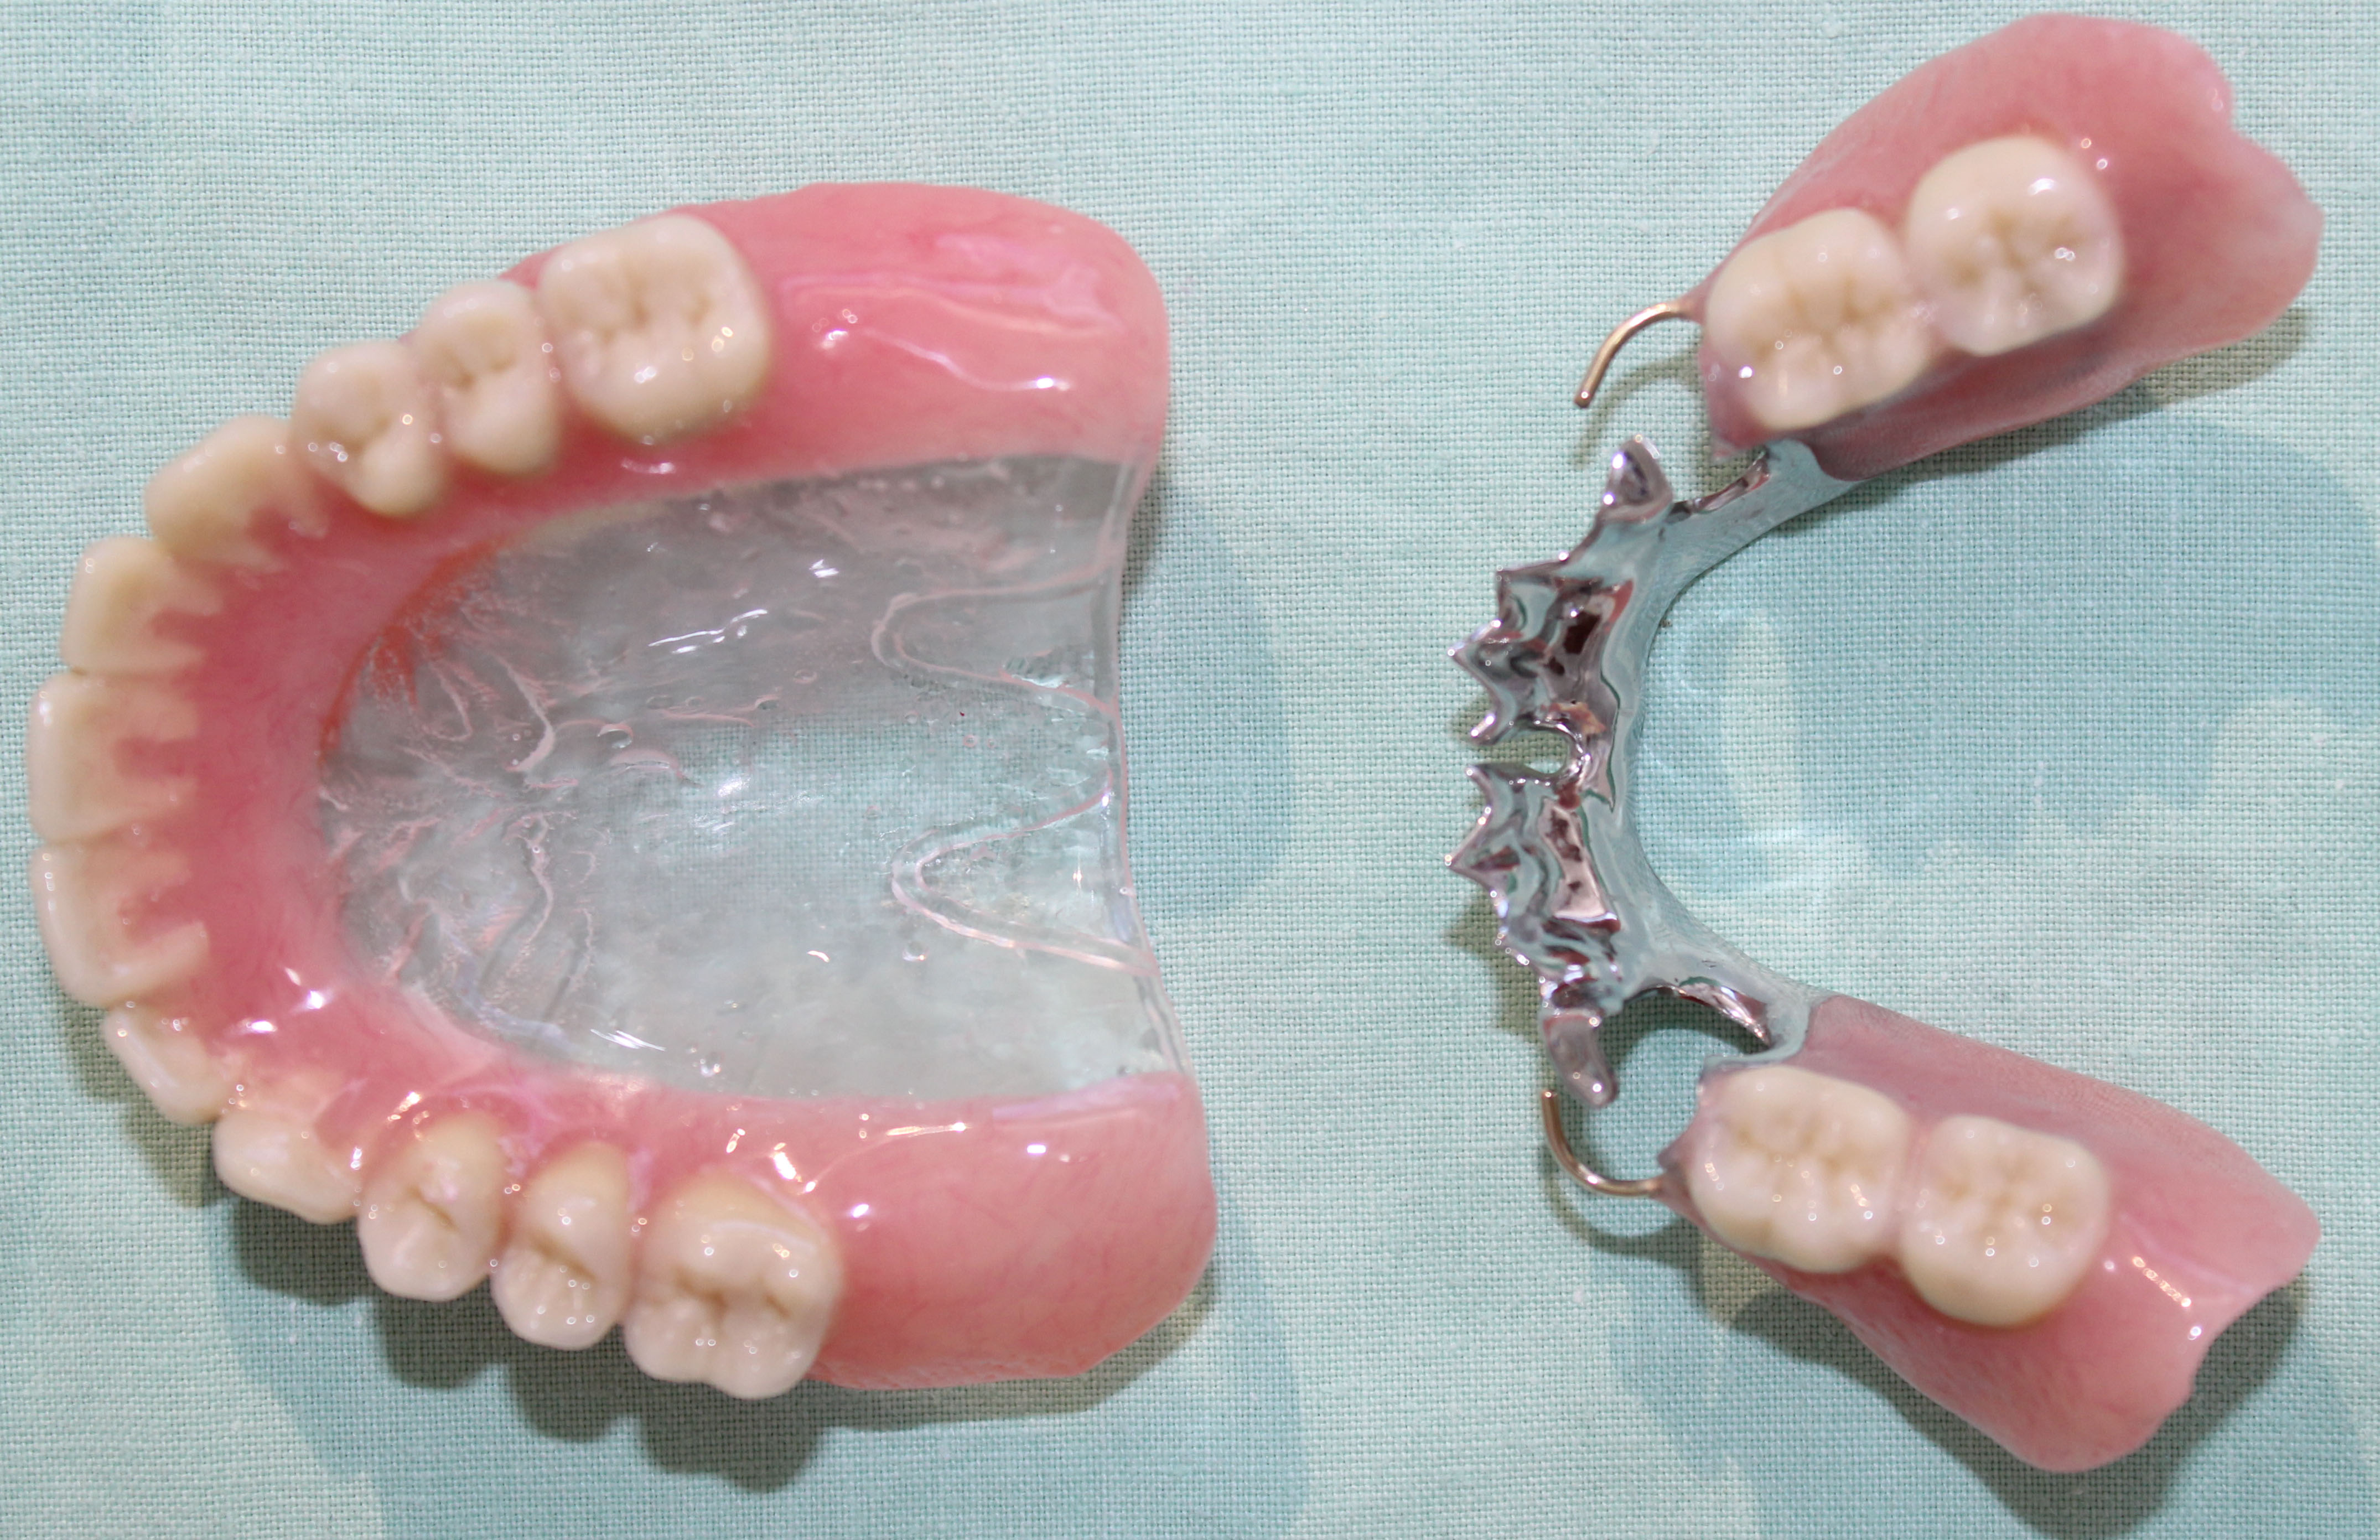

Cast Metal Partial Denture: The Most Popular Partial Denture - VTA ...

Cast Metal Partial Denture: The Most Popular Partial Denture - V…

Cast Metal Partial Denture: The Most Popular Partia…

Cast Partial Denture - Elite Dental Lab

What Is Cast Partial Denture? - GlobalDentalPro